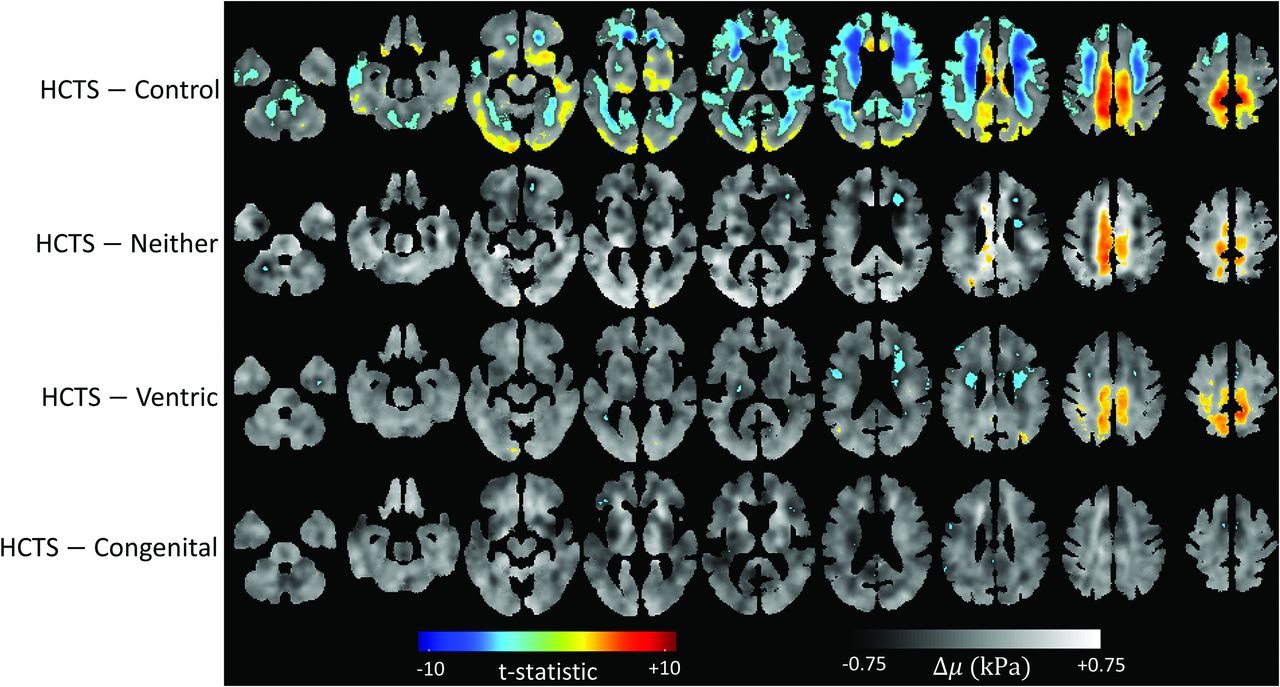

The difference maps for the stiffness between HCTS and other groups are shown in Fig 4. A gray-scale map of voxelwise differences is overlaid with a t-statistic map thresholded for statistical significance (FDR corrected with Q < 0.05). There were 93,254 voxels that were significantly different between HCTS and controls. The HCTS group had a cluster of voxels with higher stiffness at the midline vertex compared with the Ventric and Neither groups. HCTS had 6931 voxels with a significant difference in comparison with Neither and 11,364 voxels in comparison with Ventric. The HCTS and Congenital groups differed significantly in fewer voxels (735), without any discernible pattern.

Stiffness difference maps. FDR thresholded (Q < 0.05) t-statistic maps overlayed on voxelwise calculated stiffness difference maps between each group and the HCTS group. The number of voxels crossing the FDR threshold was 735 in Congenital, 11,364 in Ventric, 6931 in Neither, and 93,254 in control.

Figure 5 illustrates the difference maps for damping ratios of HCTS versus other groups. According to the thresholded t-statistic maps, damping ratio values were lower overall for the HCTS group. There were significant differences in 144,233 voxels between HCTS and control, 40,019 voxels between HCTS and Neither, 43,984 voxels between HCTS and Ventric, and none between HCTS and Congenital. A globally lower damping ratio of the HCTS group is consistent with the findings in the boxplot of Fig 3A.

Damping ratio difference maps. FDR thresholded (Q < 0.05) t-statistic maps overlayed on voxelwise calculated damping ratio difference maps between each group and the HCTS group. Congenital had no voxels crossing the FDR threshold, whereas Ventric had 43,984, Neither had 40,019, and control had 144,233.